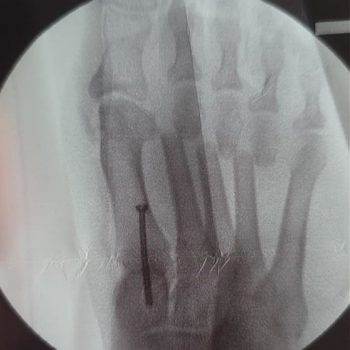

Die gute Nachricht: Wird der Sichelfuß rechtzeitig erkannt, lässt er sich bei einer Hallux-valgus-Operation häufig gleichzeitig mitbehandeln. Eine minimalinvasive Methode, die wir in unserer Praxis regelmäßig einsetzen, ist die DMMO — sie erlaubt es, die Sichelfußkomponente in demselben Eingriff zumindest deutlich zu verbessern und so das Gesamtergebnis der Hallux-valgus-Korrektur zu optimieren. Eine vollständige Korrektur des Sichelfußes ist damit zwar nicht möglich — aber eine relevante Verbesserung sehr wohl.

Häufiger ist eine operative Teilkorrektur im Rahmen anderer Eingriffe — etwa wenn gleichzeitig ein Hallux valgus operiert wird. Hier lässt sich die Sichelfußkomponente in manchen Fällen in demselben Eingriff zumindest deutlich verbessern, auch wenn eine vollständige Korrektur nicht das Ziel sein kann.